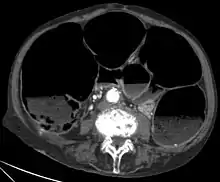

• CT-Scan showing a Cross-section of the abdomen of an elderly lady with an IPO.